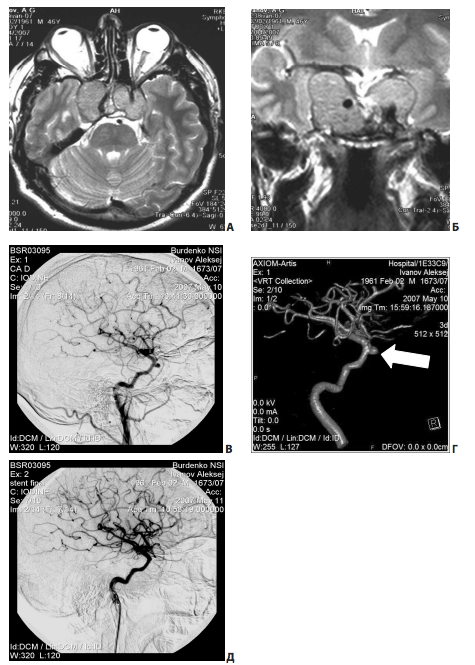

Рис. 16. Пример повреждения интракавернозного отдела левой сонной артерии на этапе удаления опухоли из полости кавернозного синуса: А, Б — МРТ до операции (большая эндо-супра-латероселлярная аденома гипофиза); В, Г — ангиография через несколько дней после операции; ложная аневризма указана стрелкой; Д — ангиография после эндоваскулярной операции

Повреждения интракавернозной части внутренней сонной артерии

Повреждение интракавернозного отдела внутренней сонной артерии является одним из наиболее опасных осложнений транссфеноидальной хирургии (как микроскопической, так и эндоскопической). Сонную артерию возможно повредить в двух случаях: либо на этапе доступа к опухоли при трепанации дна турецкого седла, если хирург слишком отклонился латерально от верной траектории, либо при манипуляциях в полости кавернозного синуса.

Клинический пример (рис. 17).

Рис. 18. Пример парциального удаления гигантской многоузловой аденомы гипофиза: А, Б — МРТ до операции; В, Г — капсула опухоли отсутствует, выделение сосудов и нервов из складок между узлами; Д, Е — КТ после операции — кровоизлияние в остатки опухоли; Ж — фото во время вскрытия умершей пациентки

Повреждение правой ВСА произошло на этапе гемостаза, после удаления опухоли из полости кавернозного синуса. При ангиографии, выполненной сразу после операции, явных признаков повреждения внутренней и наружной сонных артерий, указывающих на источник кровотечения, выявлено не было. Формирование ложной аневризмы было обнаружено при повторной ангиографии, на 8-е сут после операции (рис. 17, В, Г). По данным ангиографии, выявлены гипопластичные правые А1 и Р1. В данных условиях проводить окклюзию ВСА было нельзя. Этому пациенту был установлен стент-графт на 9-е сут после операции (рис. 17, Д). Пациент был выписан без нарастания очаговой неврологической симптоматики.

Опасность повреждения внутрикавернозной части сонной артерии при манипуляциях в кавернозном синусе, пожалуй, является основным фактором, ограничивающим возможности транссфеноидальных вмешательств.